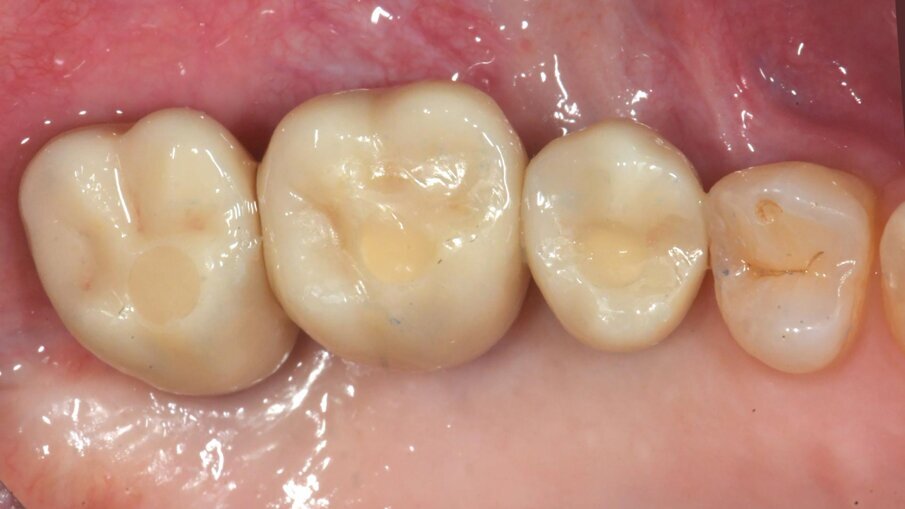

Dopo 3 mesi (T2), gli impianti sono stati esposti mediante un lembo spostato apicale per aumentare la quantità di tessuto cheratinizzato vestibolarmente agli impianti e riallineare la linea mucogengivale precedentemente spostata in direzione palatale; e sono state applicate viti di guarigione svasate per favorire una corretta guarigione trans-mucosa. Dopo 1 mese (T3), sono state eseguite corone singole in ceramica, per il primo carico funzionale e la finalizzazione provvisoria del caso, in attesa della maturazione ossea completa (Fig. 34). Dopo 6 mesi (T4), le corone sono state sostituite con corone in zirconio, per il carico funzionale e la finalizzazione definitiva degli impianti (Figg. 36-38). I controlli clinici e radiografici al primo carico funzionale, a 6 mesi, a 12 mesi, e a 24 mesi, mostrano la salute dei tessuti peri-implantari e il mantenimento dei livelli ossei peri-implantari (Fig. 39).